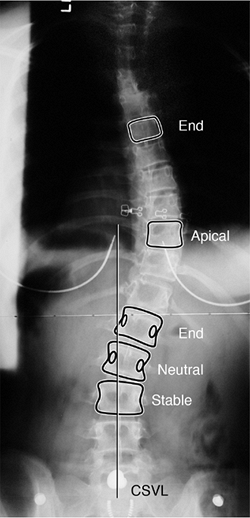

Figure 18.6

Posteroanterior radiograph demonstrating the important vertebra and landmarks which define this curvature. The two end vertebrae of the thoracic curve are at T6 and L1, with the apex or apical vertebra at T10. The end vertebrae define the ones most tilted from the horizontal, and are used for measuring the Cobb angle of the curvature. The neutral vertebra is the most cephalad vertebra that has neutrally rotated pedicles, whereas the stable vertebra is the most proximal one that remains bisected by the central sacral vertical line (CSVL). The CSVL is drawn vertically from the midsacrum. These landmarks become important in ultimately defining a curvature, as well as in determining the levels for surgical treatment.  |